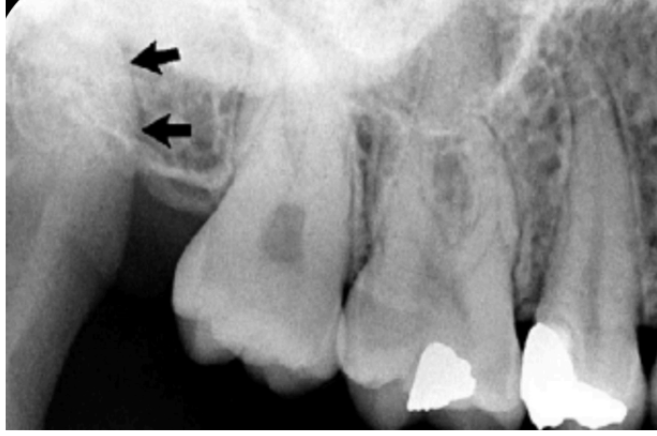

what does this show

beam hardening